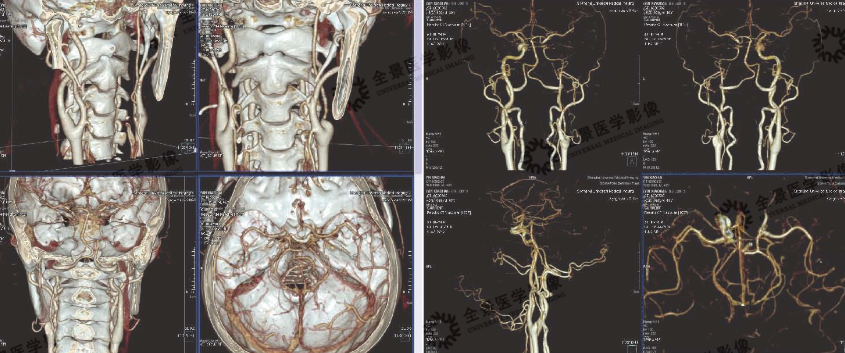

6. 头颈部血管成像

病史:中年男性,左侧眼部不适,脑梗塞病史

影像诊断:左侧颈内动脉软斑形成伴狭窄